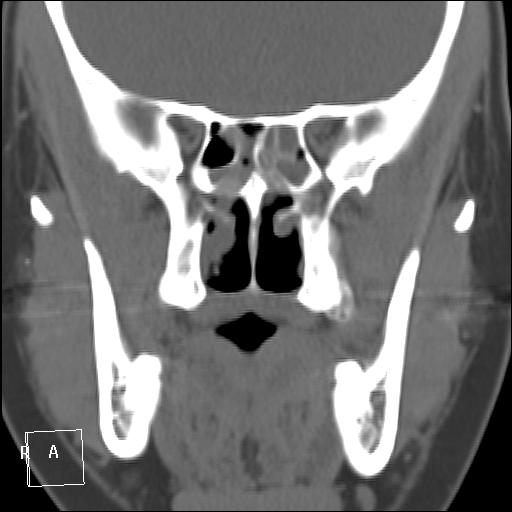

КТ ППН и носоглотки. Девушка 21 года. Полипозный риносинусит.

Госпитализирована для оперативного лечения. Удалены полипы носа. Вторым этапом планируется гайморотомия. Во время операции - подозрение на образование носоглотки. Сохраняется затруднение носового дыхания. Направлена на КТ. Категорически отказалась от контрастировния (лекарственная полиаллергия, боится).

Полип в носоглотке справа. Нарушена пневматизация придаточных пазух носа кроме левой решётчатой. В левой гайморовой на дне неясно что…

На операции визуально полипы аденоматозного типа. Какие будут гистологически после гайморотомии - сейчас трудно сказать. Если б гиперденсность была только по нижней стенке верхнечелюстной пазухи, тогда вариант с аспергиллезом на пломбировочном материале, на мой взгляд, был бы более вероятен. У девушки участки гиперденсности по всем стенкам верхнечелюстных пазух, в основной пазухе, совсем чуть - в решетчатом лабиринте слева, без костной деструкции. Без посева и гистологии - только гадать)). В носовой полости признаков грибкового поражения ЛОРы не отмечают. Но Вы правы, может иметь место изолированное поражение синусов.

Результаты гистологии после полипотомии носовой полости у нас: аденоматозные, миксоматозные полипы с признаками острого воспаления, фиброзные изменения стромы некоторых полипов. Из Твери пациентка еще не возвращалась, вестей о хоанальном полипе и результатов гайморо- и сфенотомии пока нет.